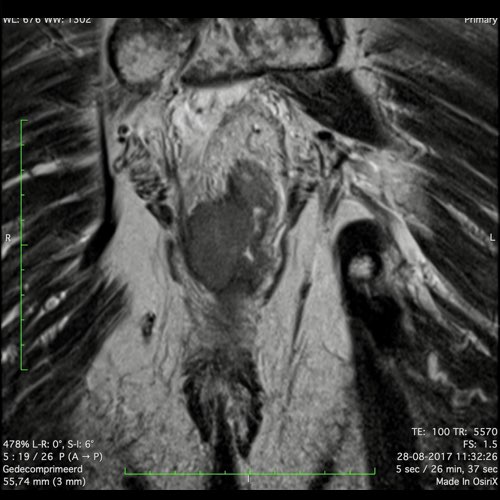

Hình ảnh

Các hình ảnh được cung cấp cho thấy ung thư biểu mô tế bào nhẫn với tình trạng dày lan tỏa thành trực tràng, hình ảnh bia bắn điển hình, và sự xâm lấn mỡ mạc treo trực tràng.